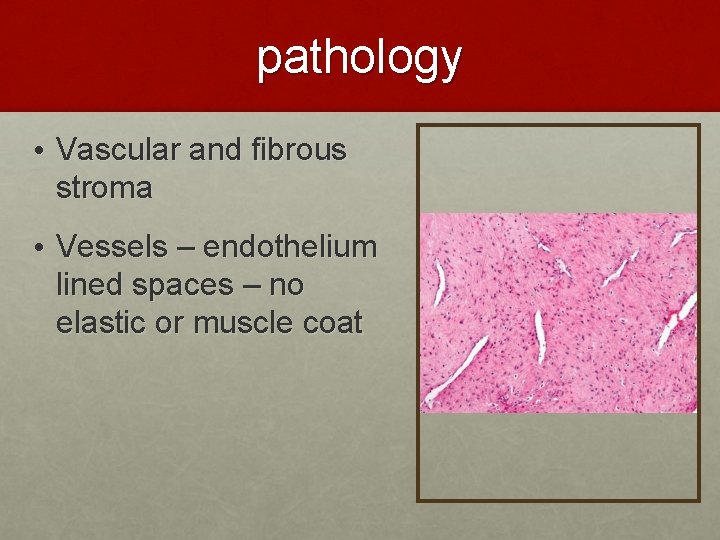

pathology • Vascular and fibrous stroma • Vessels – endothelium lined spaces – no elastic or muscle coat